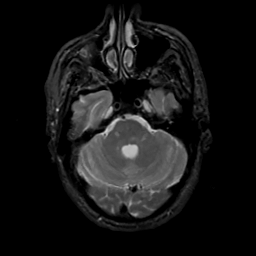

MR Study #10, April 28, 1991 -- Slice #13

[Home][Help][Clinical][Tour 1][Tour 2] Slice 13